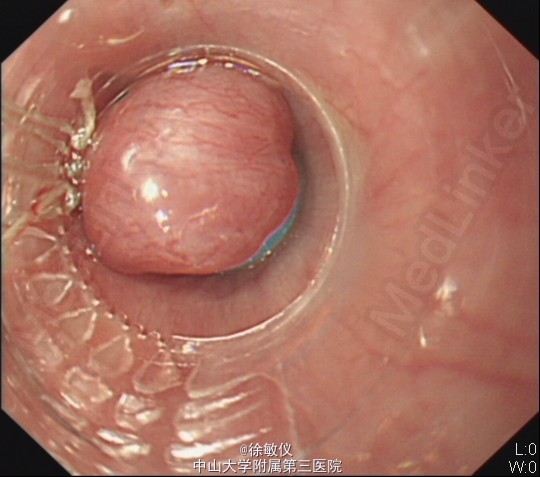

入院后予抗病毒、护肝、降门脉压、抑酸护胃、升白、营养支持等治疗。并于2015-5-13行胃镜检查,并行食管静脉曲张套扎术,结果回报:1.食管重度静脉曲张(Li+Lm,F3,CB,RC+)并套扎术;2.胃底重度静脉曲张(Lg-C,F3,CB,RC+);3.门脉高压性胃病。予请肝脏外科医师会诊,建议择期行脾切除手术。 诊断:乙型肝炎后肝硬化失代偿期 食管静脉曲张(重度,套扎术后) 重度胃底静脉曲张 门脉高压性胃肠病 脾功能亢进